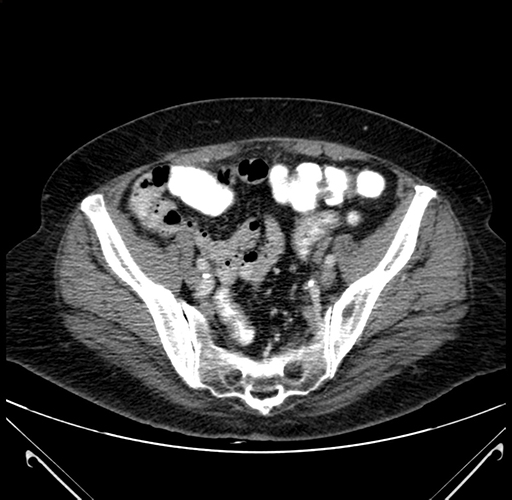

Axial Venous